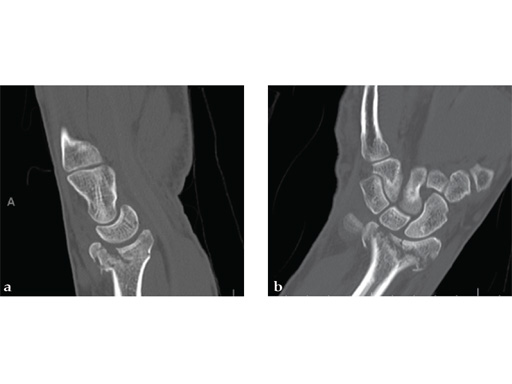

Case 1: A 62-year-old man fell on his outstretched left hand while playing tennis, sustaining an intraarticular fracture of the distal radius, Mller AO Classification 23-C3.2.

Case provided by Renato Fricker, Bruderholz, Switzerland

Case 2: A 44-year-old man sustained polytrauma following a car accident. Among his injuries was a distal radial fracture, Mller AO Classification 23-C1.

Case provided by Vitezslav Ruber, Brno, Czech Republic